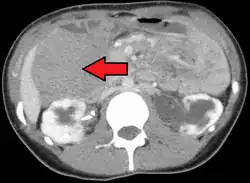

Desmoid tumor as seen on CT scan

MRI or CT imaging scans are commonly used for monitoring.[47][1]